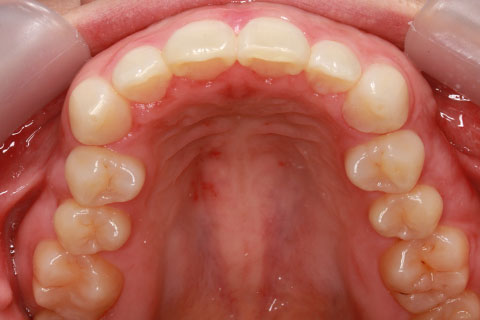

矯正期間18ヶ月

ハーフリンガル矯正2(上の歯のみ舌側矯正で治療)

治療前

治療中

治療後

- 年齢・性別

- 23歳女性

- 治療期間

- 1年6ヶ月

- 抜歯

- 上顎4番

- 治療費

- 110万円(税込み)

- 備考

- ハーフリンガル矯正

- 治療内容

- 上下前歯部凸凹の改善

- 施術の副作用(リスク)

- 裏側矯正の特性上、表側矯正と比較すると治療期間が長くかかる場合が多い。